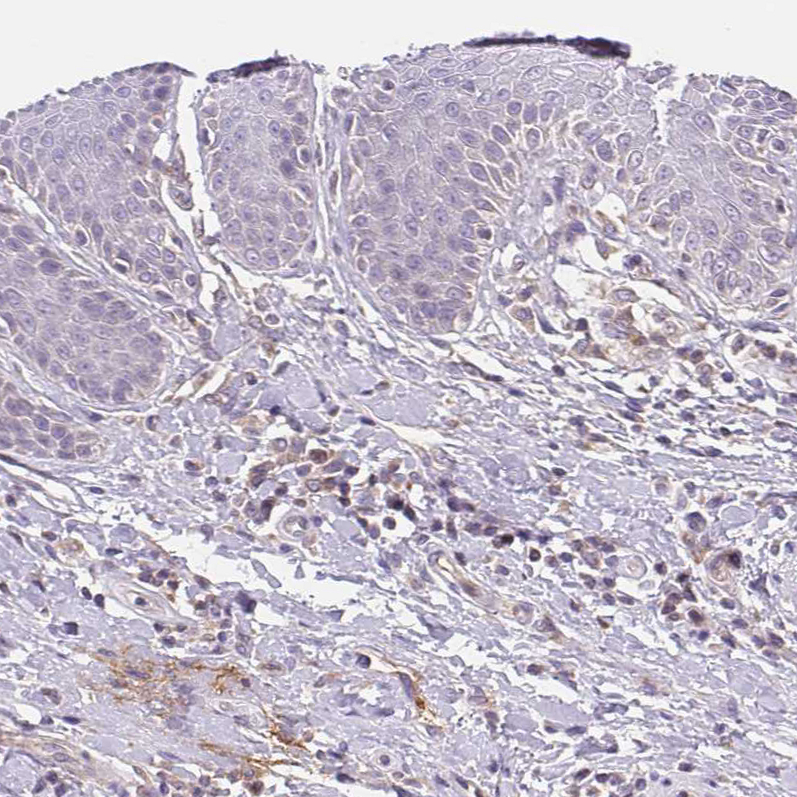

Immunohistochemical staining of human Fallopian tube moderate membranous positivity in glandular cells.